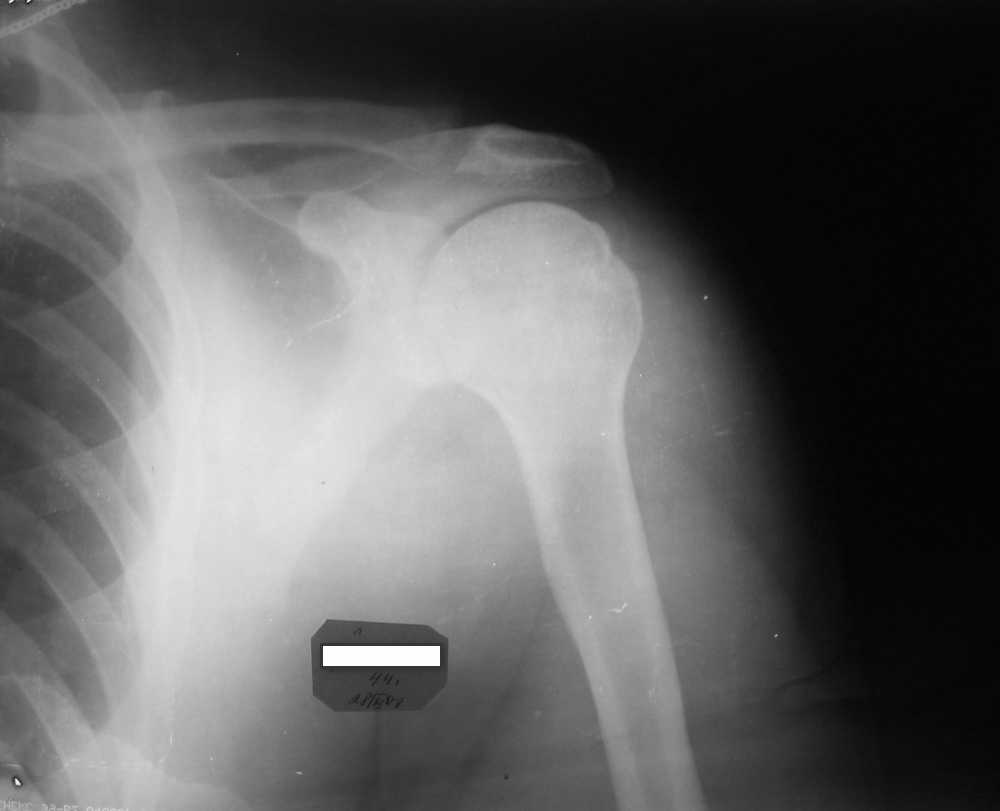

Мужчина, 45 лет. Профессионально занимается культуризмом. При жиме лёжа возникают резкие боли в левом ключично-акромиальном сочленении в течение 3 лет. В покое болей нет.

Похожая картина была и справа, однако удалось стабилизировать ситуацию с помощью консервативоного лечения.

Что, на Ваш взгляд, следует предпринять? Какие дополнительные исследования были бы полезны для определения тактики? Нет ли здесь показаний к декомпрессии подакромиального пространства? Если да, то что именно сделать?